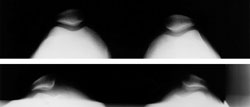

(Top) In these x-rays taken from above, both kneecaps are normally aligned within the trochlear groove. (Bottom) Here, both kneecaps have shifted out of the trochlear groove and are pulled toward the outside of the knee.

Reproduced with permission from JF Sarwark, ed: Essentials of Musculoskeletal Care, ed 4. Rosemont, IL, American Academy of Orthopaedic Surgeons, 2010